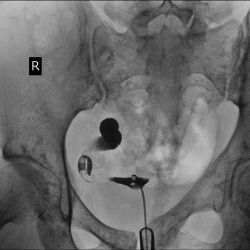

Молодая женщина 30 лет. Бесплодие. Обследуется по поводу проходимости труб. Выявленые изменения подверждены при УЗИ.